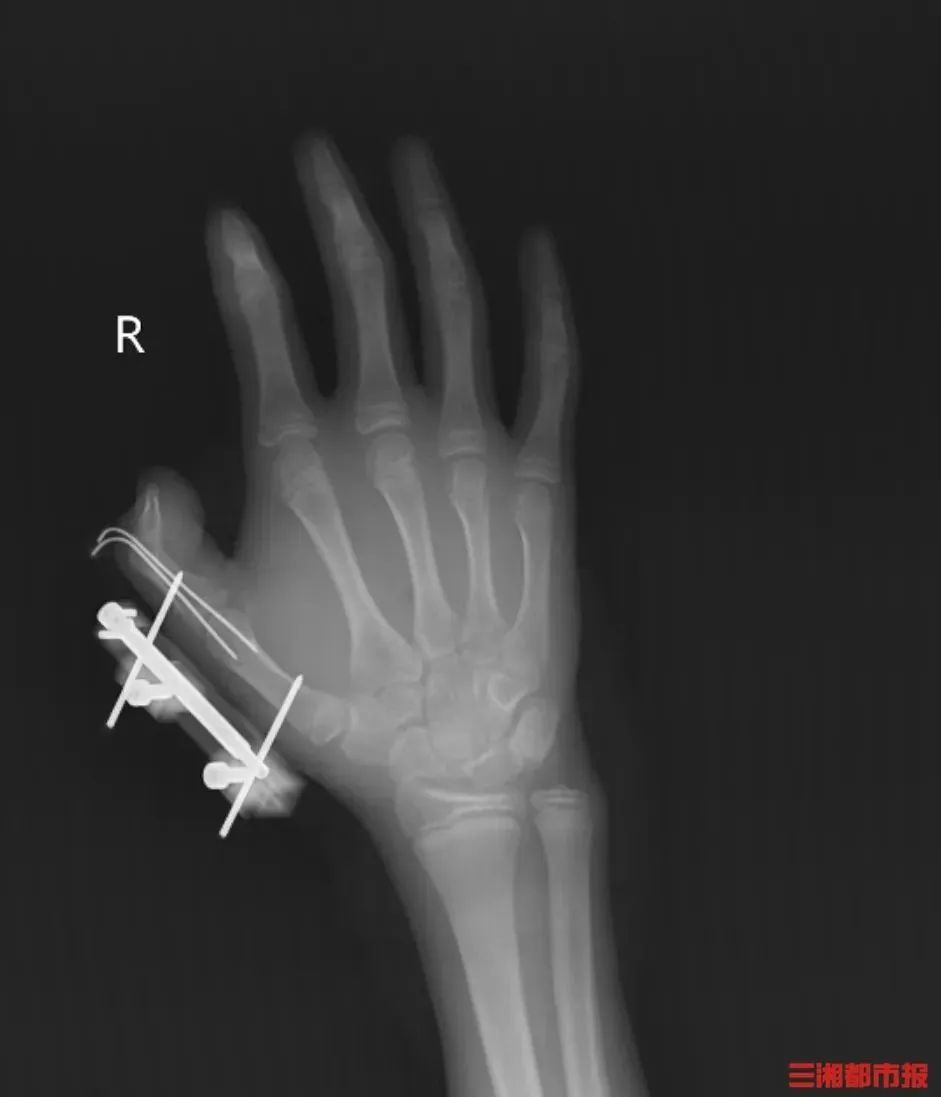

把干冰當玩具搖

14歲少年手指被炸得深可見骨